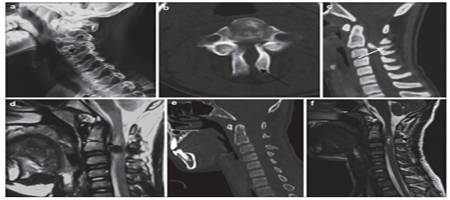

Rare bilateral C3 cervical spondylolysis:Report of four cases and a literature review

Objective:

To review and discuss the etiology, diagnosis and treatment C3 of bilateral cervical spondylolysis.

Methods:

This was a retrospective review of the clinical features, imaginge findings, and treatment of 4 cases of bilateral C3 cervical spondylolysis, with a review of the literature.

Results:

A 21-year-old woman, a 26-year-old man, a 14-year-old boy, and a 46-year-old man were diagnosed with bilateral C3 cervical spondylolysis. The patients had characteristic bilateral clefts between the articular pillar and the facets of C3, as well as spina bifida on CT. Although spondylolisthesis was not observed, spinal cord compression was definitive. All patients underwent posterior decompression with satisfactory results.

Conclusions:

C3 cervical spondylolysis is rare condition. The cause is most likely congenital. Diagnosis is dependent on characteristic radiological features. Surgical treatment is the first choice.